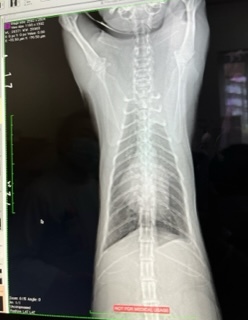

・レントゲン検査

肺も白い部分がだいぶ減ってきました。